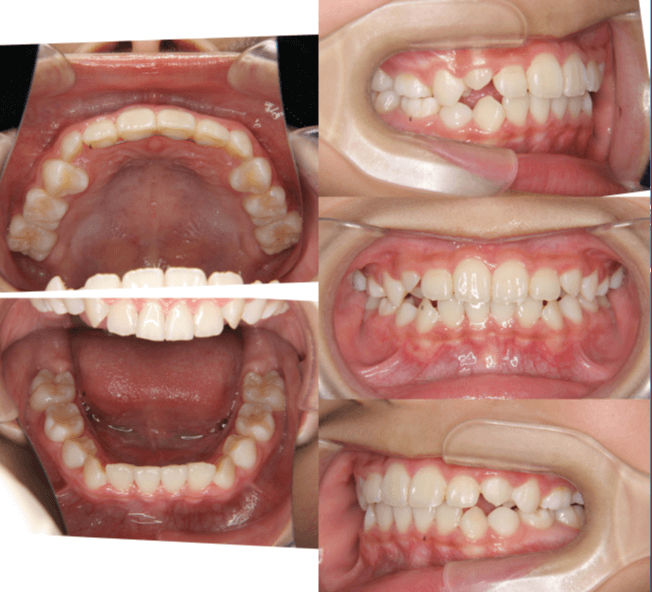

| 年齢・性別 | 8歳9ヶ月の女児 |

|---|---|

| 主訴 | 歯並びの乱れを気にされて来院された患者様です。将来的なスペース不足と歯のねじれ(翼状捻転)が懸念されました。 |

| 治療期間・回数 | 2年10ヶ月・19回 |

| 費用 | 430,000円(税別) |